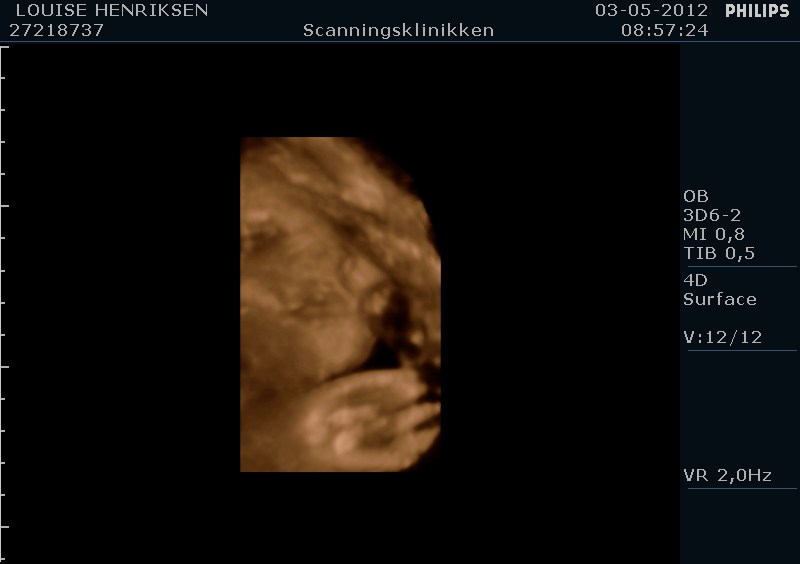

I dag skulle manden overraskes med en 4 d scanning.... og hans far var også med det var også en overraskelse, samt den lille prins....han fik bind for øjene og vi kørte mod scanning klinikken.... vi fik nogle gode sekvenser af bettemanden.. men han fylder en del derinde nu, så billederne blev ikke voldsomt gode.. men nogle fik vi dag...jeg skulle i morgen være 32 fulde uger.. mne scanningen i dag vidste34+4 dage yiarks.... jeg skal til at være færdig med den bachelor..... han vejede efter målene 1871 gram.....

så han var en fin basse...